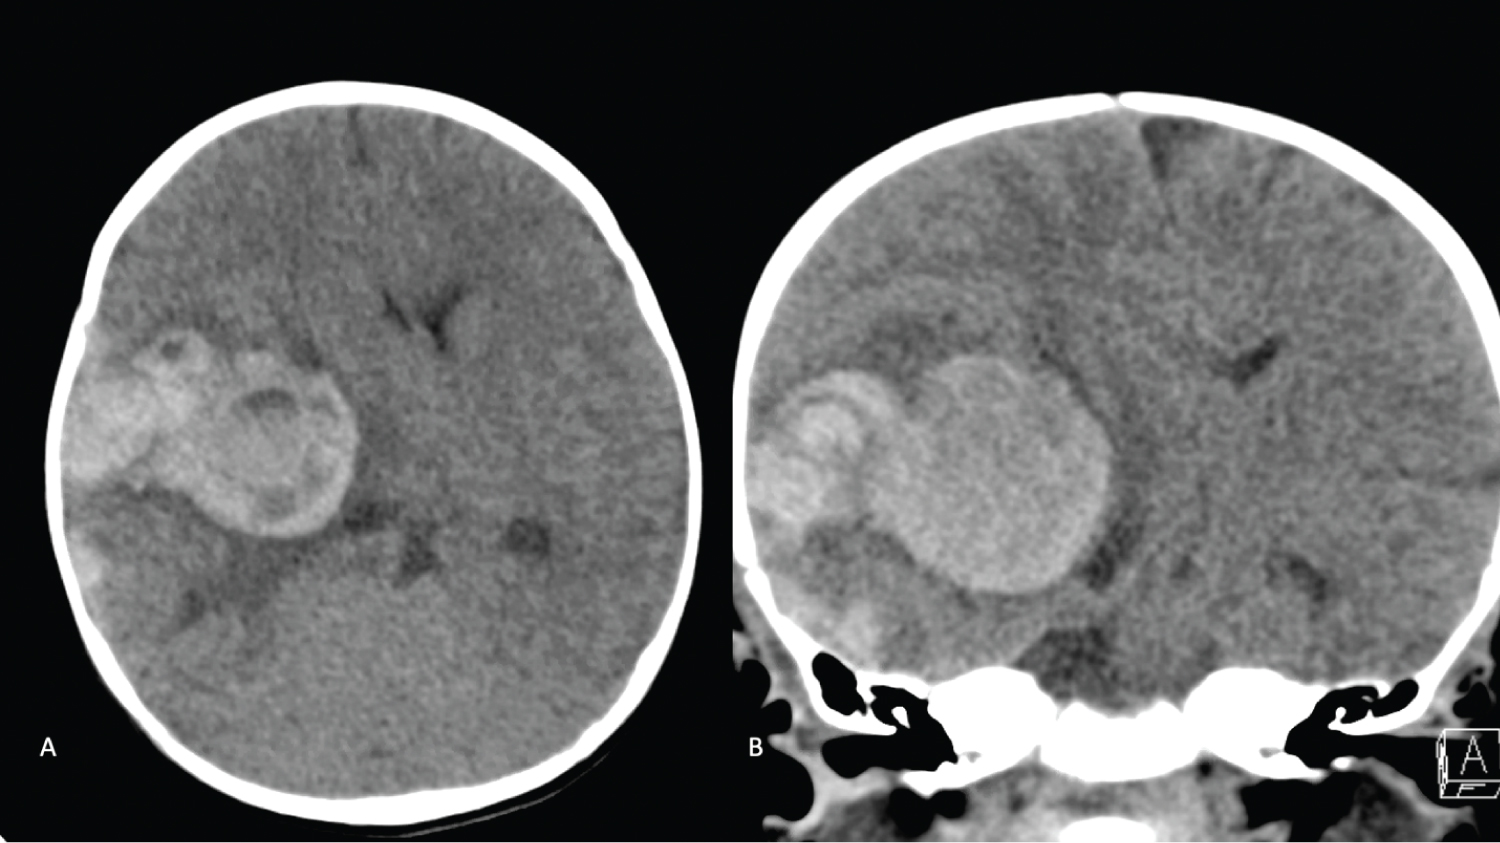

Given the history of HA, a computed tomography (CT) scan of the head was ordered, which demonstrated a 5.6 × 3.7 cm acute intraparenchymal hematoma (IPH) centered on the right basal ganglia with associated 12 mm of leftward midline shift and right uncal herniation (Figure 1). At this time, the patient was given 500 IU factor VIII (Advate), 10g mannitol (1 g/kg), and 200 mg levetiracetam (20 mg/kg). CT angiogram was negative for an underlying vascular malformation or aneurysm (Figure 2). Given the significant midline shift as well as uncal and subfalcine herniation, the patient was taken to the operating room emergently for a right-sided decompressive hemicraniectomy and evacuation of the hematoma.

Figure 1: A) Non-Contrast Axial; B) Coronal. CT the head demonstrating a 5.6 × 3.7 cm acute intraparenchymal hematoma centered in the right basal ganglia with an associated 12 mm leftward midline shift and right sided uncal herniation with an asymmetrically enlarged temporal horn of the right lateral ventricle. There are also multifocal right frontal-temporal-parietal acute extra-axial hemorrhages as well as a right posterior falcine/tentorial subdural hematoma. View Figure 1